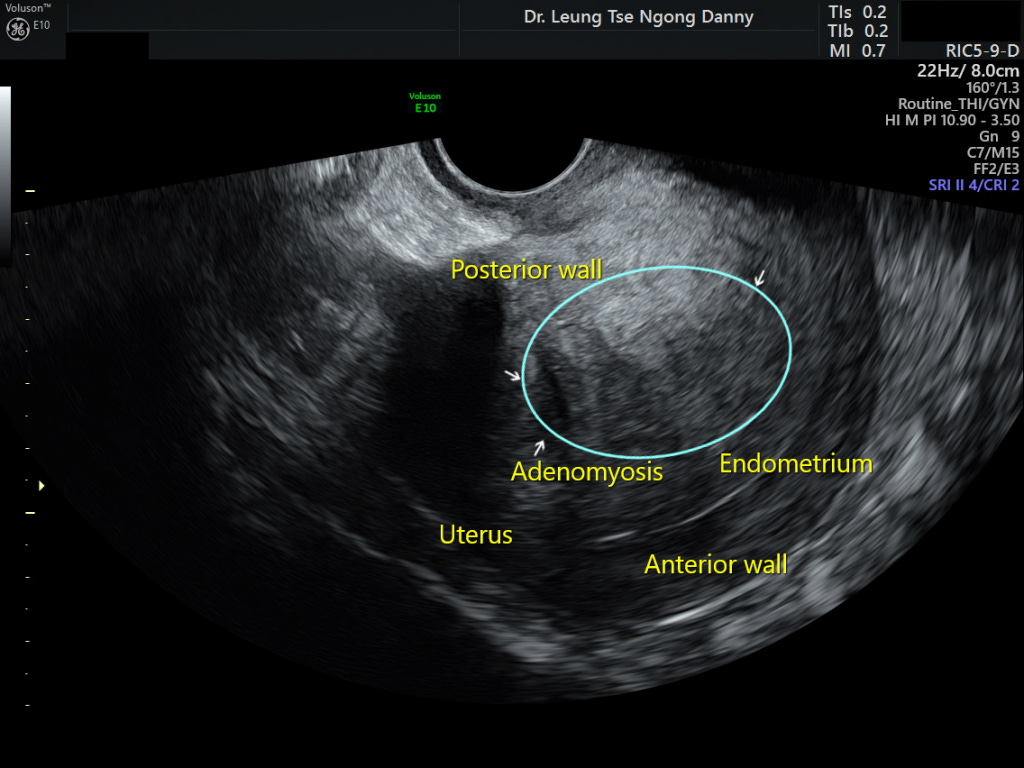

The first point of diagnosis is a trans-vaginal ultrasonography and you can typically expect to see a posterior thickening of the myometrium along with instances of myometrial cysts, linear striations radiating out from the endometrium, and a general loss of a clearly defined endometrial border coupled with an increased myometrial heterogeneity.

With an ectopic growth of endometrium-type tissue, we also see an increased vascularity in the region, observed through a Colour Doppler view. This vascularity also to a great extent helps us define the inner margins of the adenoma.

You can appreciate the core of the diseased region in the image above. Because of a lack of a clear margin of the disease in adenomyosis, this vascularity is a good approximation of that margin. In a different edition, we will talk about how this information aids surgical planning.